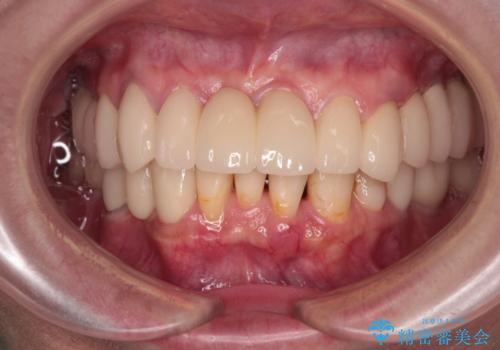

- 以前通院していた医院で、奥歯のインプラント埋入、前歯部のインビザライン矯正を行ったものの、そのまま放置してしまったとのことで来院された患者様です。

下顎前歯や上顎奥歯などをワイヤー装置により部分矯正を行い、歯列を整えた上でインプラン部分を含めてオールセラミッククラウンにて補綴治療を行うこととしました。

- 治療費の目安: 450万円(税込)費用は治療当時の料金となります

インプラント上の仮歯がボロボロになり、前歯に非常に負担のかかる状態であったため、早急に奥歯の仮歯を修復し、矯正治療、奥歯の補綴治療、前歯の補綴治療と順々に進めて行きました。